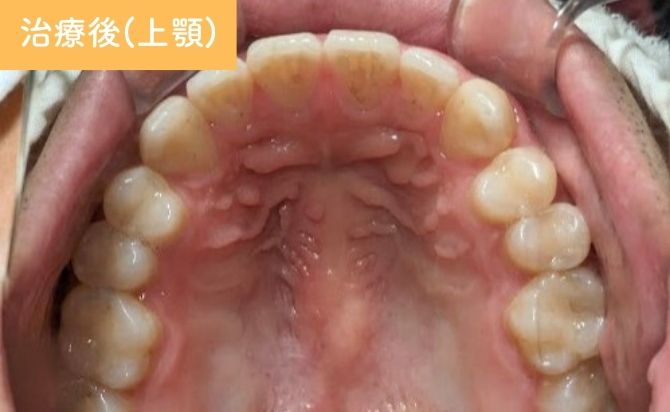

歯並びの変化(上)

治療終了時には、上顎前歯の歯間空隙が閉鎖され、前歯部の開咬も改善しました。上下前歯の前突感が軽減され、歯列弓も自然な形態に整っています。

前歯部の見た目が大きく改善しただけでなく、噛み合わせも安定し、機能面・審美面の両立が図られた症例となりました。